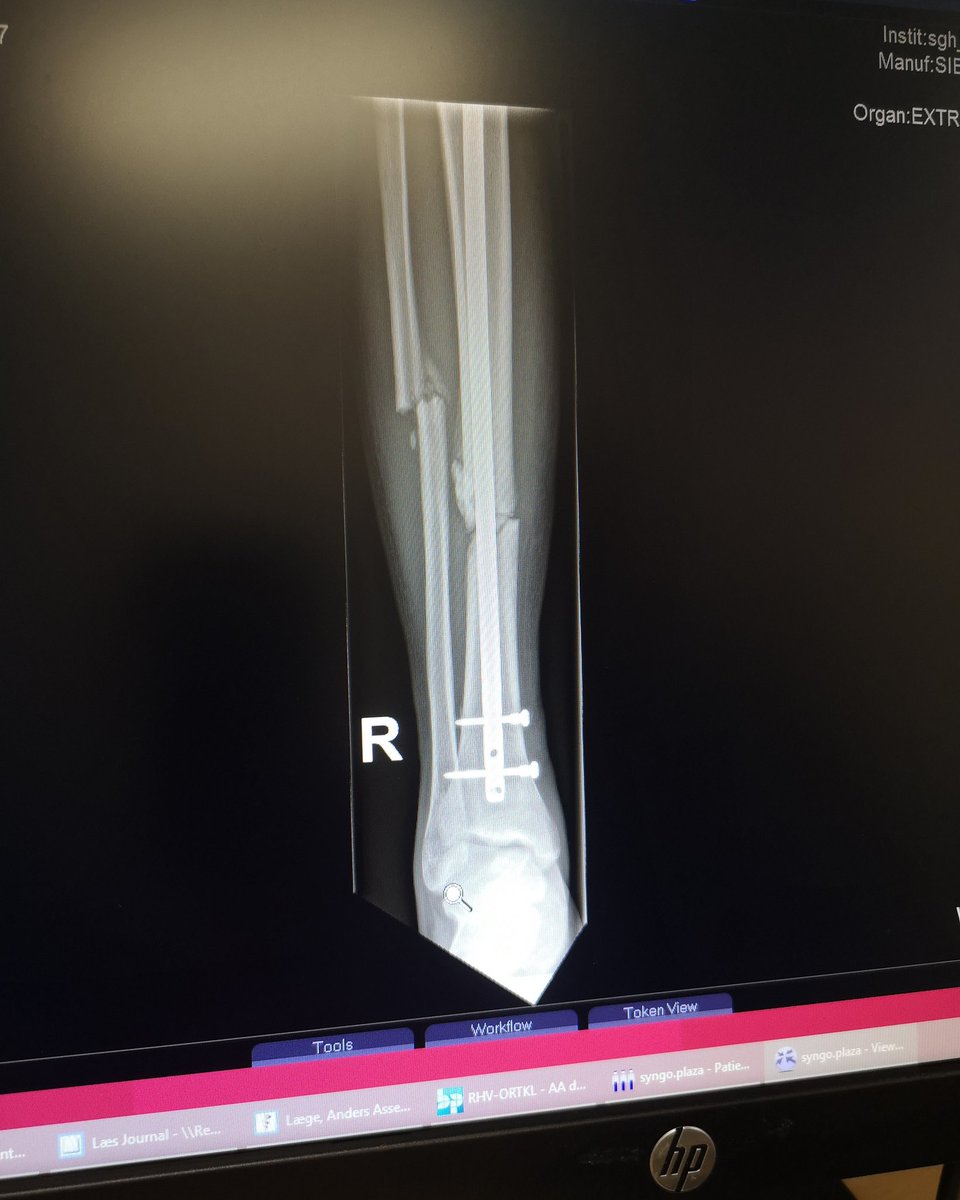

Post- 7week surgery - leg looks like shit, but doctors says it's looking super good

anyway I'll spend a few more weeks on the turbo, but just super happy to be able to get my heart rate up

#rehab pic.twitter.com/uMj3UDEWKL